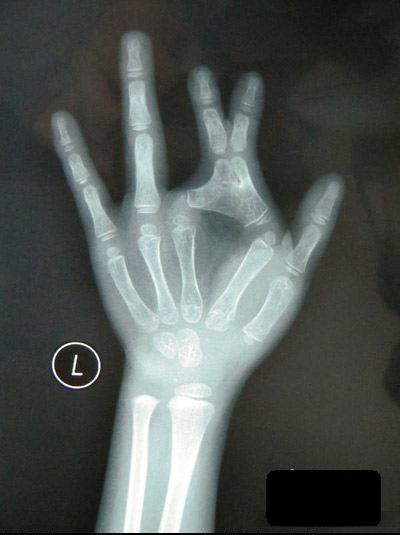

Cô bé có tên Tiểu Na ở Trung Quốc sinh ra đã có xương tay hình cái kéo, nên từ nhỏ em đã không thể chơi trò oẳn tù tì giống như những em nhỏ bình thường khác.

Trò chơi oẳn tù tì vốn là một trò chơi vô cùng đơn giản của các bé, nhưng với Tiểu Na (6 tuổi) người tỉnh Trùng Khánh, Trung Quốc thì đây quả là trò chơi trong mơ, bởi bàn tay em bị dị tật bẩm sinh từ nhỏ với xương bàn tay hình chiếc kéo.

6 năm trước, Tiểu Na ra đời tại một vùng nông thôn của tỉnh Trùng Khánh. Bế con gái trên tay, cha em đã vô cùng kinh ngạc khi thấy trên bàn tay trái của Tiểu Na, đốt ngón cái và ngón trỏ dính liền vào nhau, trông giống hệt một chiếc kéo.

Do hoàn cảnh gia đình khó khăn nên không có tiền chạy chữa, bên cạnh đó tay phải vẫn hoạt động bình thường nên cũng không gây trở ngại lớn cho cuộc sống sinh hoạt của em. Mãi đến năm Tiểu Na 3 tuổi, cha mẹ em mới quyết định đưa em đi khám bệnh, nhưng hầu hết các bệnh viện đều không đảm bảo sẽ chữa trị được cho em.

Mãi đến khi tới bệnh viện Nhi đồng, các bác sỹ mới quyết định tiến hành phẫu thuật thẩm mỹ bàn tay cho Tiểu Na. “Đây là một ca phẫu thuật khó, bởi ngón tay thứ 2 và thứ 3 của cháu đã bị biến dạng giống hình một chiếc kéo, khiến nửa ngón tay còn lại phát triển không bình thường, cái khó nhất là làm thế nào để cấy da lên phần xương ngón tay sau khi được tách ra”, bác sỹ phẫu thuật cho Tiểu Na cho biết.